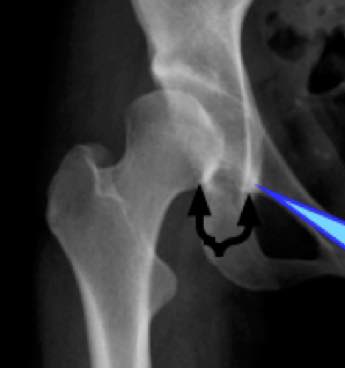

It's not clear in my mind from what you describe whether this is hip and capsular pain from a hypermobile hip (no signs of dysplasia, no sloping acetabulum, no unroofed femoral ball?) or a true femoral nerve condition. Try and answer the above as accurately as you can to get a more accurate diagnosis.

Could you try and send me a copy of your pelvic x-ray?